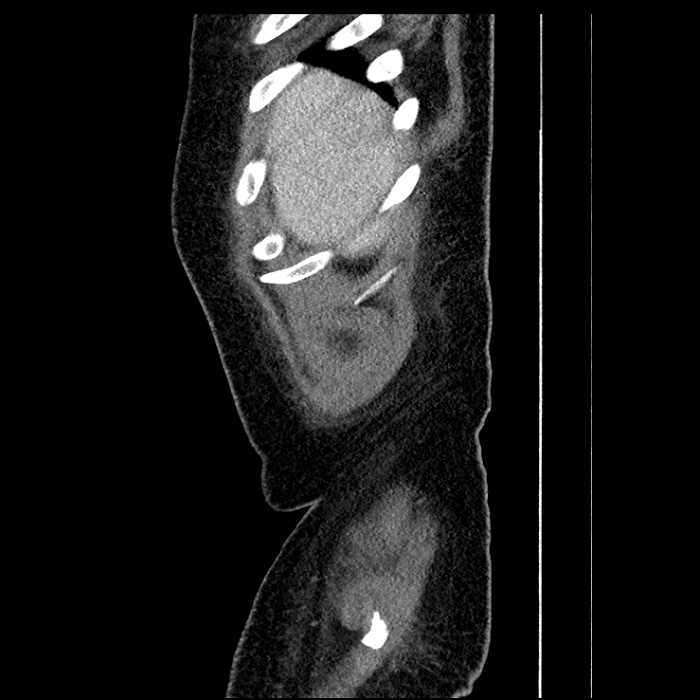

Age: 63

Sex: Male

Indication: Abdominal pain

• Large fluid density structure in hepatic segments 7 and 8 measuring 10 x 7 x 7 cm with internal septation and circumferential ill-defined low density compatible with edema

• Peripherally enhancing subcapsular collections along the anterior margin of the left hepatic lobe measuring 3 x 1 cm and 2 x 1 cm

• Hepatic abscess

Acute sigmoid diverticulitis complicated by a small contained perforation and a large abscess in the right hepatic lobe. Additional small subcapsular abscesses along the anterior margin of the left hepatic lobe.

• The classic CT imaging appearance is a double target sign with internal low density surrounded by an internal enhancing rim (capsule) and a low density external rim (edema)

Hepatic abscess showing the double target sign with low density internally surrounded by a thin inner enhancing rim (red arrow) and ill-defined outer low density rim (yellow arrow). Blue arrow indicates an internal septation. Red arrows: additional smaller subcapsular abscesses. Red arrow: focal contained perforation associated with diverticulitis.